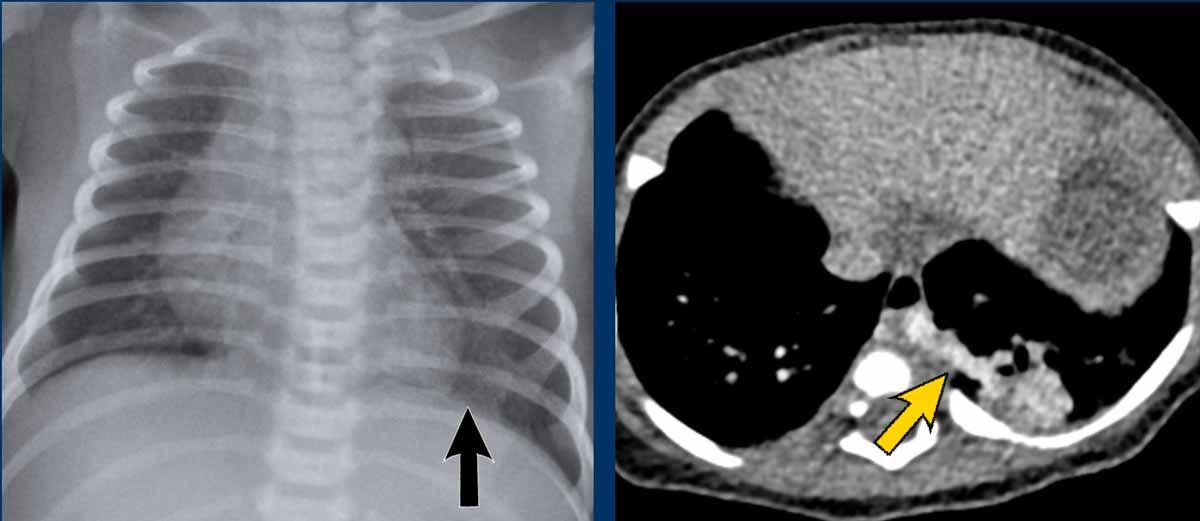

29 tuần + 1, ngày đầu tiên. CPAP.

Nhìn vào hình ảnh lần đầu.

Những phát hiện là gì?

Findings:

- Reticulogranular opacification

of lungs - Air bronchogram

- Consolidation in the right lower lobe

- Heart, vessels and

diaphragm are poorly defined. - Đặt sai vị trí catheter tĩnh mạch rốn (mũi tên), có thể nằm trong tĩnh mạch phổi.

- Nasogastric tube (NG tube) in good position.

Đây là trường hợp nặng của hội chứng suy hô hấp (RDS).

Chẩn đoán phân biệt bao gồm nhiễm trùng phổi do tình trạng đông đặc không đối xứng.